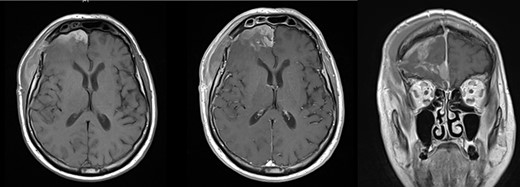

Axial pre- (left) and post-contrast T1-weigted MRI brain (middle) showed relief of the mass effect with correction of the midline shift. Coronal image (right) confirmed residual tumor along the right of the falx cerebri.

MRI brain was suggestive of meningioma and confirmed residual tumor (Fig. 2). Histopathological findings of perivascular epithelioid cells arranged loosely in sheets with a papillary architecture, immunohistochemical positive staining for vimentin, epithelial membrane antigen (EMA) and progesterone as well as increased Ki67 (5%) fraction, led to a final report of PM World Health Organization Grade III. No other abnormal mass was found on clinical examination.